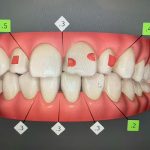

皆さま、こんにちは。 アルデブラン・デンタルクリニック神戸三宮院 歯科助手のYです。 精密検査を行ってから約2週間が経ち、治療計画が出来上がりました。 今回はクリンチェック(治療計画)についてご紹介します。 クリ […]